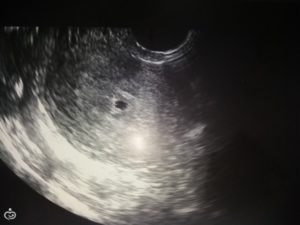

Существует расхожее мнение, что во время УЗИ-диагностики врач может перепутать плодное яйцо с наростом. Ведь при значительных размерах образований некоторые симптомы их нахождения в матке схожи с «интересным положением». Однако оно имеет под собой очень мало оснований.

Квалифицированный врач без труда отличит, полип или беременность он видит на мониторе приспособления. Плодное яйцо темного цвета и округлой формы, тогда как нарост светлый, имеющий цилиндрическую форму.

Отличить полипозное новообразование в матке от плодного яйца не составит труда – они отличаются как по форме, так и по цвету. Плодное яйцо более округлое и имеет темную окраску, а полип – более светлый.

Плодное яйцо — анэхогенное образование, то есть темное пятно круглой или овальной формы с четким контуром. Это потому что внутри содержится жидкость, в ней выделяется светлый эмбрион. Увидеть плод можно уже на 2 неделе.